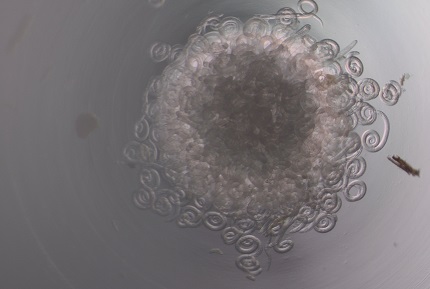

Trichinella mikroskoobi all

Keeritsussid on mikroskoopilised ümarussid, mis põhjustavad inimesel keeritsusstõbe ehk trihhinelloosi. Inimene nakatub parasiidi vastseid sisaldava liha või piisava kuumtöötluseta lihatoodete söömisel. Nakkusallikaks Eestis on sagedamini metssiga, harvem karu. Seetõttu on oluline, et liha oleks enne toidulauale jõudmist eelnevalt nõuetekohaselt kontrollitud.